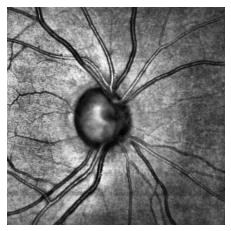

Fairness in artificial intelligence models has gained significantly more attention in recent years, especially in the area of medicine, as fairness in medical models is critical to people's well-being and lives. High-quality medical fairness datasets are needed to promote fairness learning research. Existing medical fairness datasets are all for classification tasks, and no fairness datasets are available for medical segmentation, while medical segmentation is an equally important clinical task as classifications, which can provide detailed spatial information on organ abnormalities ready to be assessed by clinicians. In this paper, we propose the first fairness dataset for medical segmentation named Harvard-FairSeg with 10,000 subject samples. In addition, we propose a fair error-bound scaling approach to reweight the loss function with the upper error-bound in each identity group, using the segment anything model (SAM). We anticipate that the segmentation performance equity can be improved by explicitly tackling the hard cases with high training errors in each identity group. To facilitate fair comparisons, we utilize a novel equity-scaled segmentation performance metric to compare segmentation metrics in the context of fairness, such as the equity-scaled Dice coefficient. Through comprehensive experiments, we demonstrate that our fair error-bound scaling approach either has superior or comparable fairness performance to the state-of-the-art fairness learning models. The dataset and code are publicly accessible via https://ophai.hms.harvard.edu/harvard-fairseg10k.